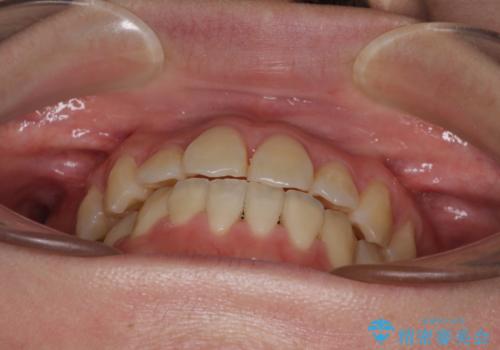

ハーフリンガル 反対咬合の改善

- 前歯の反対咬合を気にして来院された患者様です。

目立ちにくい装置での治療をご希望とのことで、上顎が裏側装置、下顎が表側装置のハーフリンガルにより矯正治療を行うこととしました。

下顎の歯列全体を後方に動かす場合、さまざまリスクを伴うため慎重に行う必要があり、さらには移動量に限界があるため、治療計画は無理のないものとしなければなりません。

下顎左右の奥にアンカーボルトを使用して、無理のない範囲で後方に移動させ、きれいに仕上げることができました。